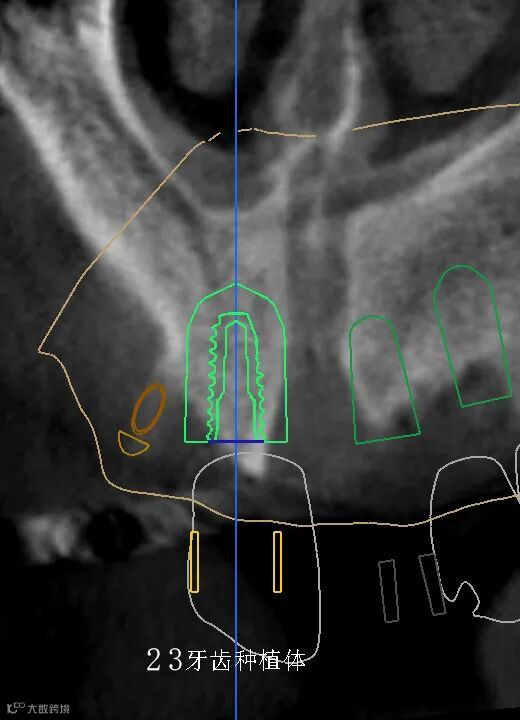

数字化种植手术规划与导板设计

临床种植手术过程